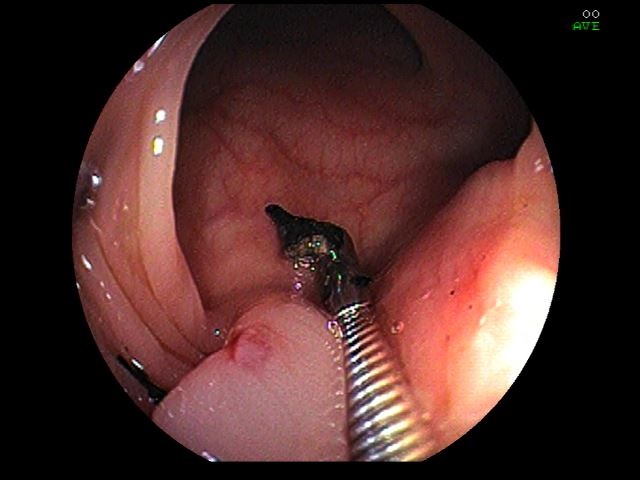

4. Foreign body in the sigmoid colon

º¹ÅëÀ» ÁÖ¼Ò·Î ³»¿øÇÑ 40´ë ¿©¼ºÀÇ ´ëÀå³»½Ã°æÀÔ´Ï´Ù. Ãæ¼öµ¹±â ÀýÁ¦¼ú(10³âÀü), Á¦¿ÕÀý°³(6³âÀü)ÀÇ º´·ÂÀÌ ÀÖ´Â ºÐÀ¸·Î, ¾à 5³âÀüºÎÅÍ ¿À¸¥ÂÊ ¹è²Å¾Æ·§ºÎÀ§°¡ °Çµå¸®°Å³ª ´©¸£¸é ¾ÆÇ Áõ»óÀÌ ÀÖ¾ú½À´Ï´Ù. º»¿ø ³»¿ø½Ã Ç÷¾×°Ë»ç¿¡¼­ ö°áÇ̼º ºóÇ÷, ½Åü°Ë»ç¿¡¼­ ¹è²Å¿ìÃøÇϺΠ¾ÐÅëÀÌ ÀÖ¾î ´ëÀå³»½Ã°æÀ» ½ÃÇàÇÏ¿´½À´Ï´Ù. Ç×¹®¿¬ 20cm »ó¹æ, distal S-colon¿¡ ºÎ½ÄµÈ µÕ±Ù¸Ó¸®¸¦ °¡Áø ¹Ù´ÃÀÌ 45µµ »ç¼±À¸·Î ÀåÁ¡¸·À» ¶Õ°í ÀÖÀ¸¸ç, ÁÖº¯ Á¡¸·Àº ºÎÁ¾°ú ÀÛÀº ±Ë¾çÀÌ µ¿¹ÝµÇ¾î ÀÖ¾ú½À´Ï´Ù. À̹°ÀÌ ²ÈÈù ºÎÀ§¸¦ Á¶Á÷°Ë»ç°âÀÚ·Î °üÂû½Ã µÕ±Ù ¸Ó¸®ºÎºÐÀº ¶³¾îÁ® ³ª°¡°í ¹Ù´ÃÇüÅÂÀÇ ºÎÀ§¸¸ ÀåÁ¡¸·¿¡ ²ÈÇô ÀÖ¾ú½À´Ï´Ù. ÃâÇ÷°ú õ°øÀÇ À§Ç輺À¸·Î À̹°Àº Á¦°Å ¾Ê°í CT È®ÀÎ ÈÄ Á¦°ÅÇϵµ·Ï ȯÀÚ¿¡°Ô ¼³¸íÇÏ¿´°í »ó±Þº´¿øÀ¸·Î Àü¿øÇÏ¿´½À´Ï´Ù.